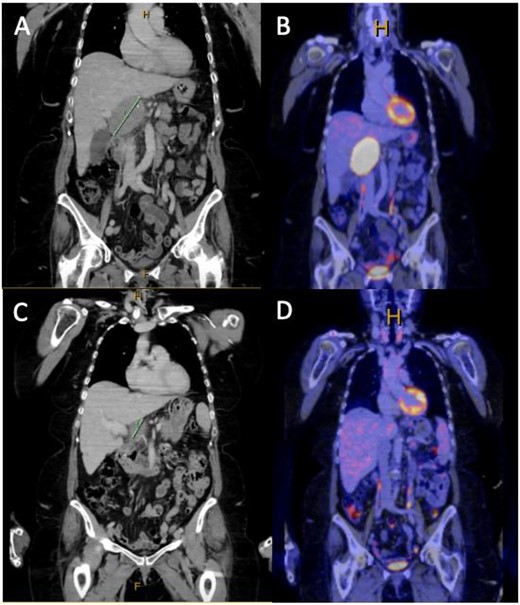

A 72-year-old female was referred to the hepatopancreaticobiliary (HPB) surgery clinic with an FDG avid exophytic lesion measuring 44 × 56 × 78 mm, thought to be arising from the caudate lobe of the liver projecting inferiorly into the portacaval space (Fig. 1A and B). The patient’s oncological history was significant for a previous excision of a left infraorbital/cheek lesion 2 years prior. This initial cutaneous lesion was found to be a superficial spreading melanoma with a Breslow thickness of 2.8 mm with no lymphovascular invasion or ulceration; the margins were clear, however, <5 mm, overall staged as T3aNxM0. The patient was offered a wide local excision and sentinel lymph node biopsy; however, the patient declined and proceeded with close surveillance with six monthly PET scans. The patient was otherwise fit and well with minimal past medical history.

(A and B) Coronal slice of surveillance CT and FDG PET showing a 44 × 56 × 78 mm PET avid exophytic lesion abutting the caudate lobe extending into portocaval space suspicious for metastatic melanoma, given the patients history of cutaneous melanoma; (C and D) coronal slice of CT and FDG PET post three cycles of dual immunotherapy, showing complete metabolic response and significant reduction in size of the metastatic lesion demonstrated in (A) and (B).

Given the high FDG avidity of the caudate lesion endoscopic ultrasound and fine needle aspirate, biopsies were arranged. Histopathology from this biopsy was consistent with a diagnosis of metastatic melanoma. Based on the imaging and tissue diagnosis, the patient was discussed at the HPB multidisciplinary team meeting, and decision was made for the commencement of immunotherapy with potential for surgical resection if there is adequate disease response. The patient was proceeded with dual immunotherapy (ipilimumab and nivolumab), and upon completion of three cycles of immunotherapy, there was a repeat PET/CT scan. The repeat PET scan showed complete metabolic response of the lesion abutting the caudate lobe, which was no longer FDG avid and had reduced in size significantly. The patient underwent a portohepatic lymphadenectomy and cholecystectomy. No macroscopic disease was observed within the peritoneal cavity and a hard 30 × 40 mm nodule was resected from within the hepatoduodenal ligament along with a lymph node packet containing several visible nodes from porta-hepatis to duodenum, including hepatic nodes. Histopathology from this operation showed granulomatous reaction with no viable malignancy remaining. The patient was discharged from HPB surgical clinics 4 weeks postoperatively with an appropriate medical oncology follow-up. The patient is currently 2 months postsurgery and has commenced single-agent immunotherapy with nivolumab as an adjuvant treatment with a planned repeat PET scan when treatment is completed.